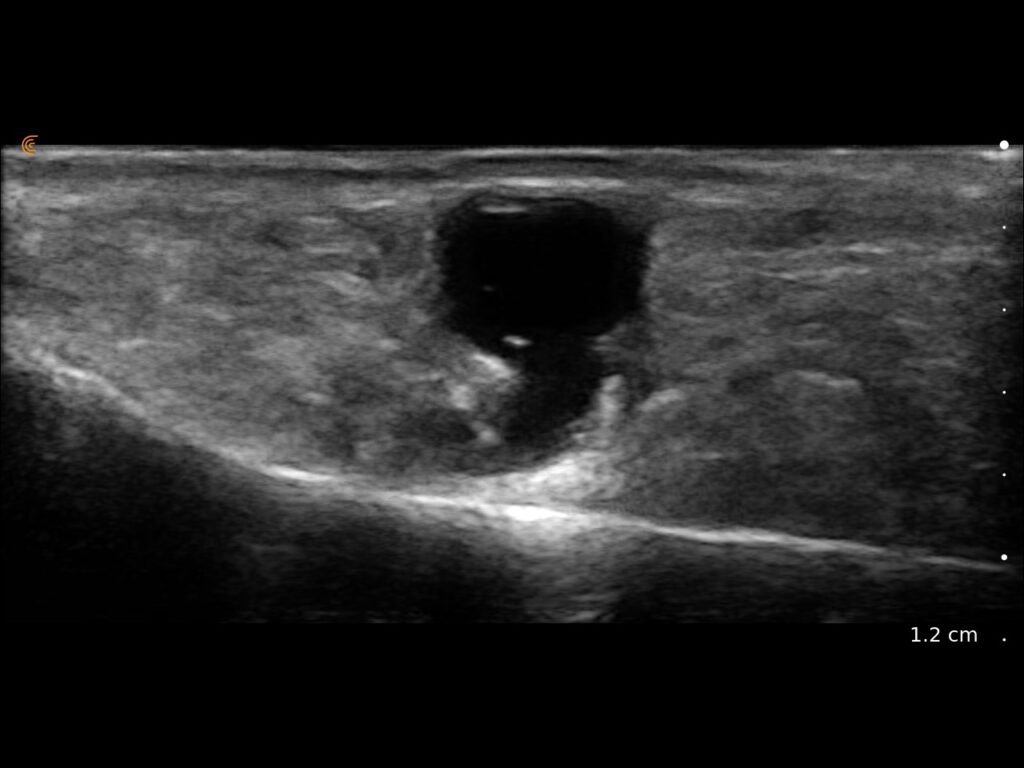

Procedures Just Got More Precise.

Visualize targets in real time to deliver PRP or cortisone—even in complex joints. Instantly diagnose sprains, tears, and effusions, and make confident decisions about surgical intervention